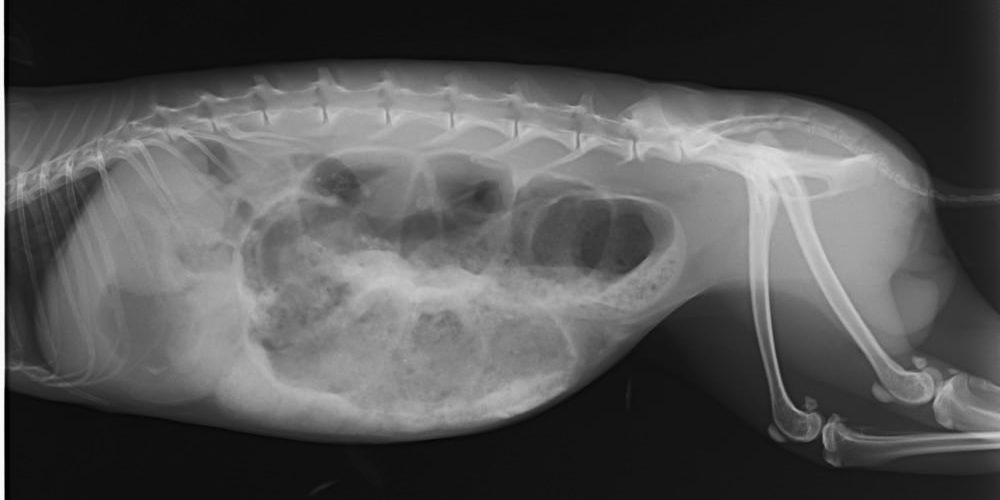

Megfelelő kondícióban lévő törpenyúl, testtömege 2 kg. A testnyílások környékén szennyeződés nem látható. A légzőszervek részéről kóros elváltozás nem tapasztalható. A mellkas felett hallgatózva ritmusos, szabályos szívhangok hallhatók. Szőre borzolt, fénytelen. Szemmel láthatóan bágyadt, a környezet ingereire alig reagál, összekuporodva ül, időnként remeg. A has tapintása során annak kifejezett puffadtsága nagy mennyiségű gáz jelenléte észlelhető. Fogait éber állapotban otoscoppal vizsgálva nem volt látható kopási rendellenesség. Az egész testről készített laterolateralis beállítású röntgenfelvételen a bélcsatorna számos szakaszának jelentős tágulata, gázzal való kiteltsége látható (lásd mellékelt Röntgen lelet.)